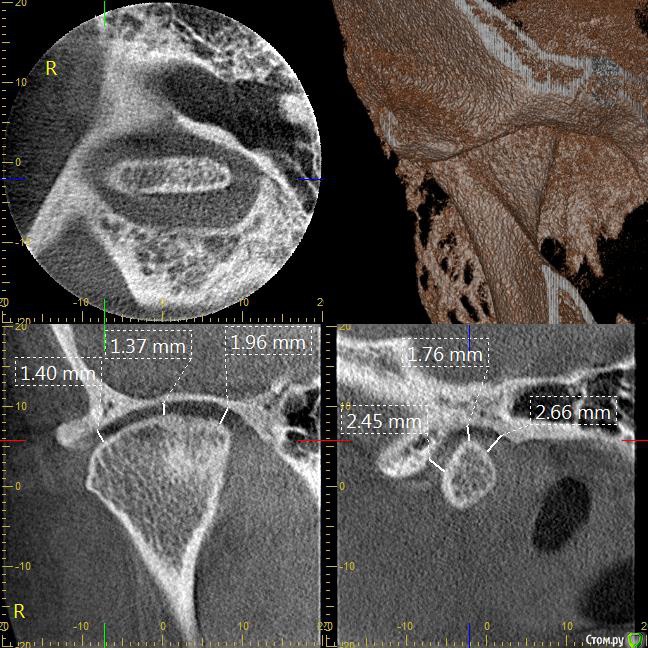

Мне 31 год. В детстве мне выбили верхний зуб 2-ку. Собираюсь лечиться брекетами, а потом вставлять имплант на место двойки. Но у меня есть еще проблеми с ВНЧС (с детства болит, хруст, щелчки), делала недавно КТ ВНЧС, диагноз артрит или артроз. Ходила к многим специалистам, все говорят разное. Надо ли проводить лечения капой моей дисфункции ВНЧС до установки брекетов или после установки брекетов?